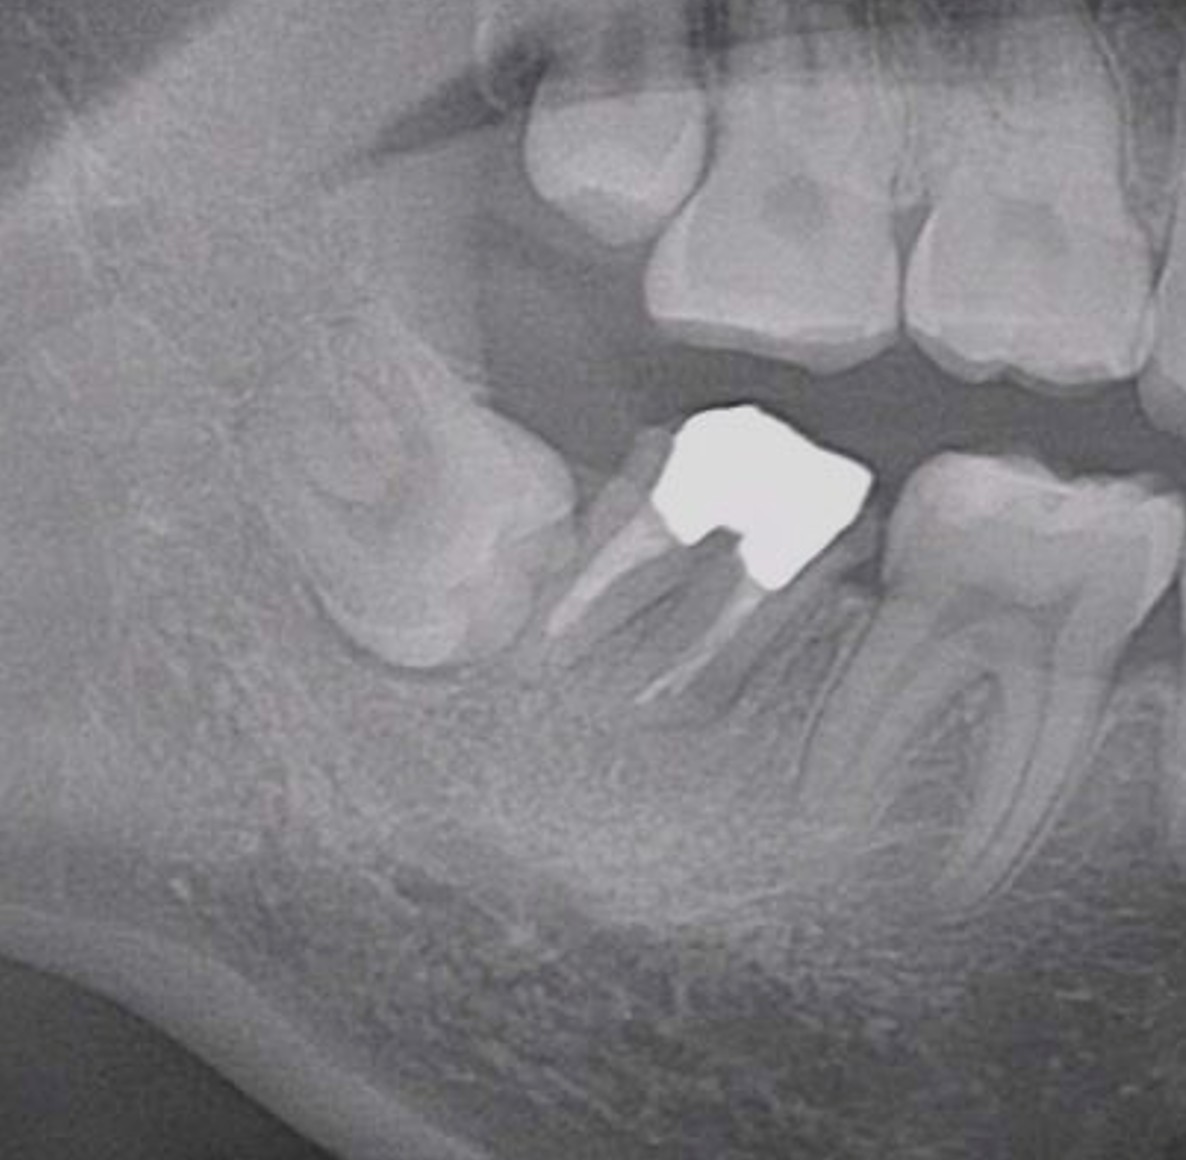

症例4

右下親知らずを右下第二大臼歯へ移植

| 患者様データ | 20代 女性 |

| 来院時の主訴 | 「右下奥歯で噛むと痛い。」 |

| 医院の診断 | 歯根破折 |

| 治療費 | 総額:255,000円(税抜) 【内訳】 歯牙移植150,000円、ファイバーポストコア20,000円、セラミック治療85,000円 |

| リスクと副作用 | ①根管治療歯は長期的には破折するリスク ②長期的なメインテナンスが必要 ③歯根の外部吸収 |

抜歯が必要になった際に余っている親知らずがあれば移植歯として利用することができます。 術前に撮影したCT画像から3Dプリンターを用いて親知らずのレプリカを作製することで、親知らずが乾燥することを防ぎ、成功率が上がるよう努力しています。 |